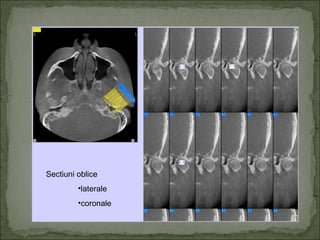

Sectiuni oblice

•laterale

•coronale